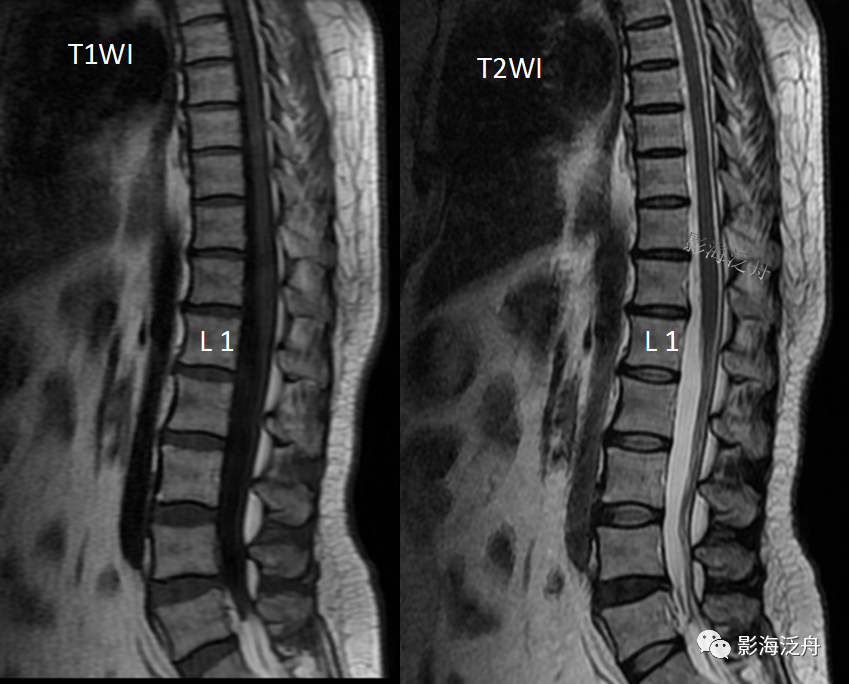

• 椎体血管瘤影像学诊断

椎体血管瘤影像学诊断